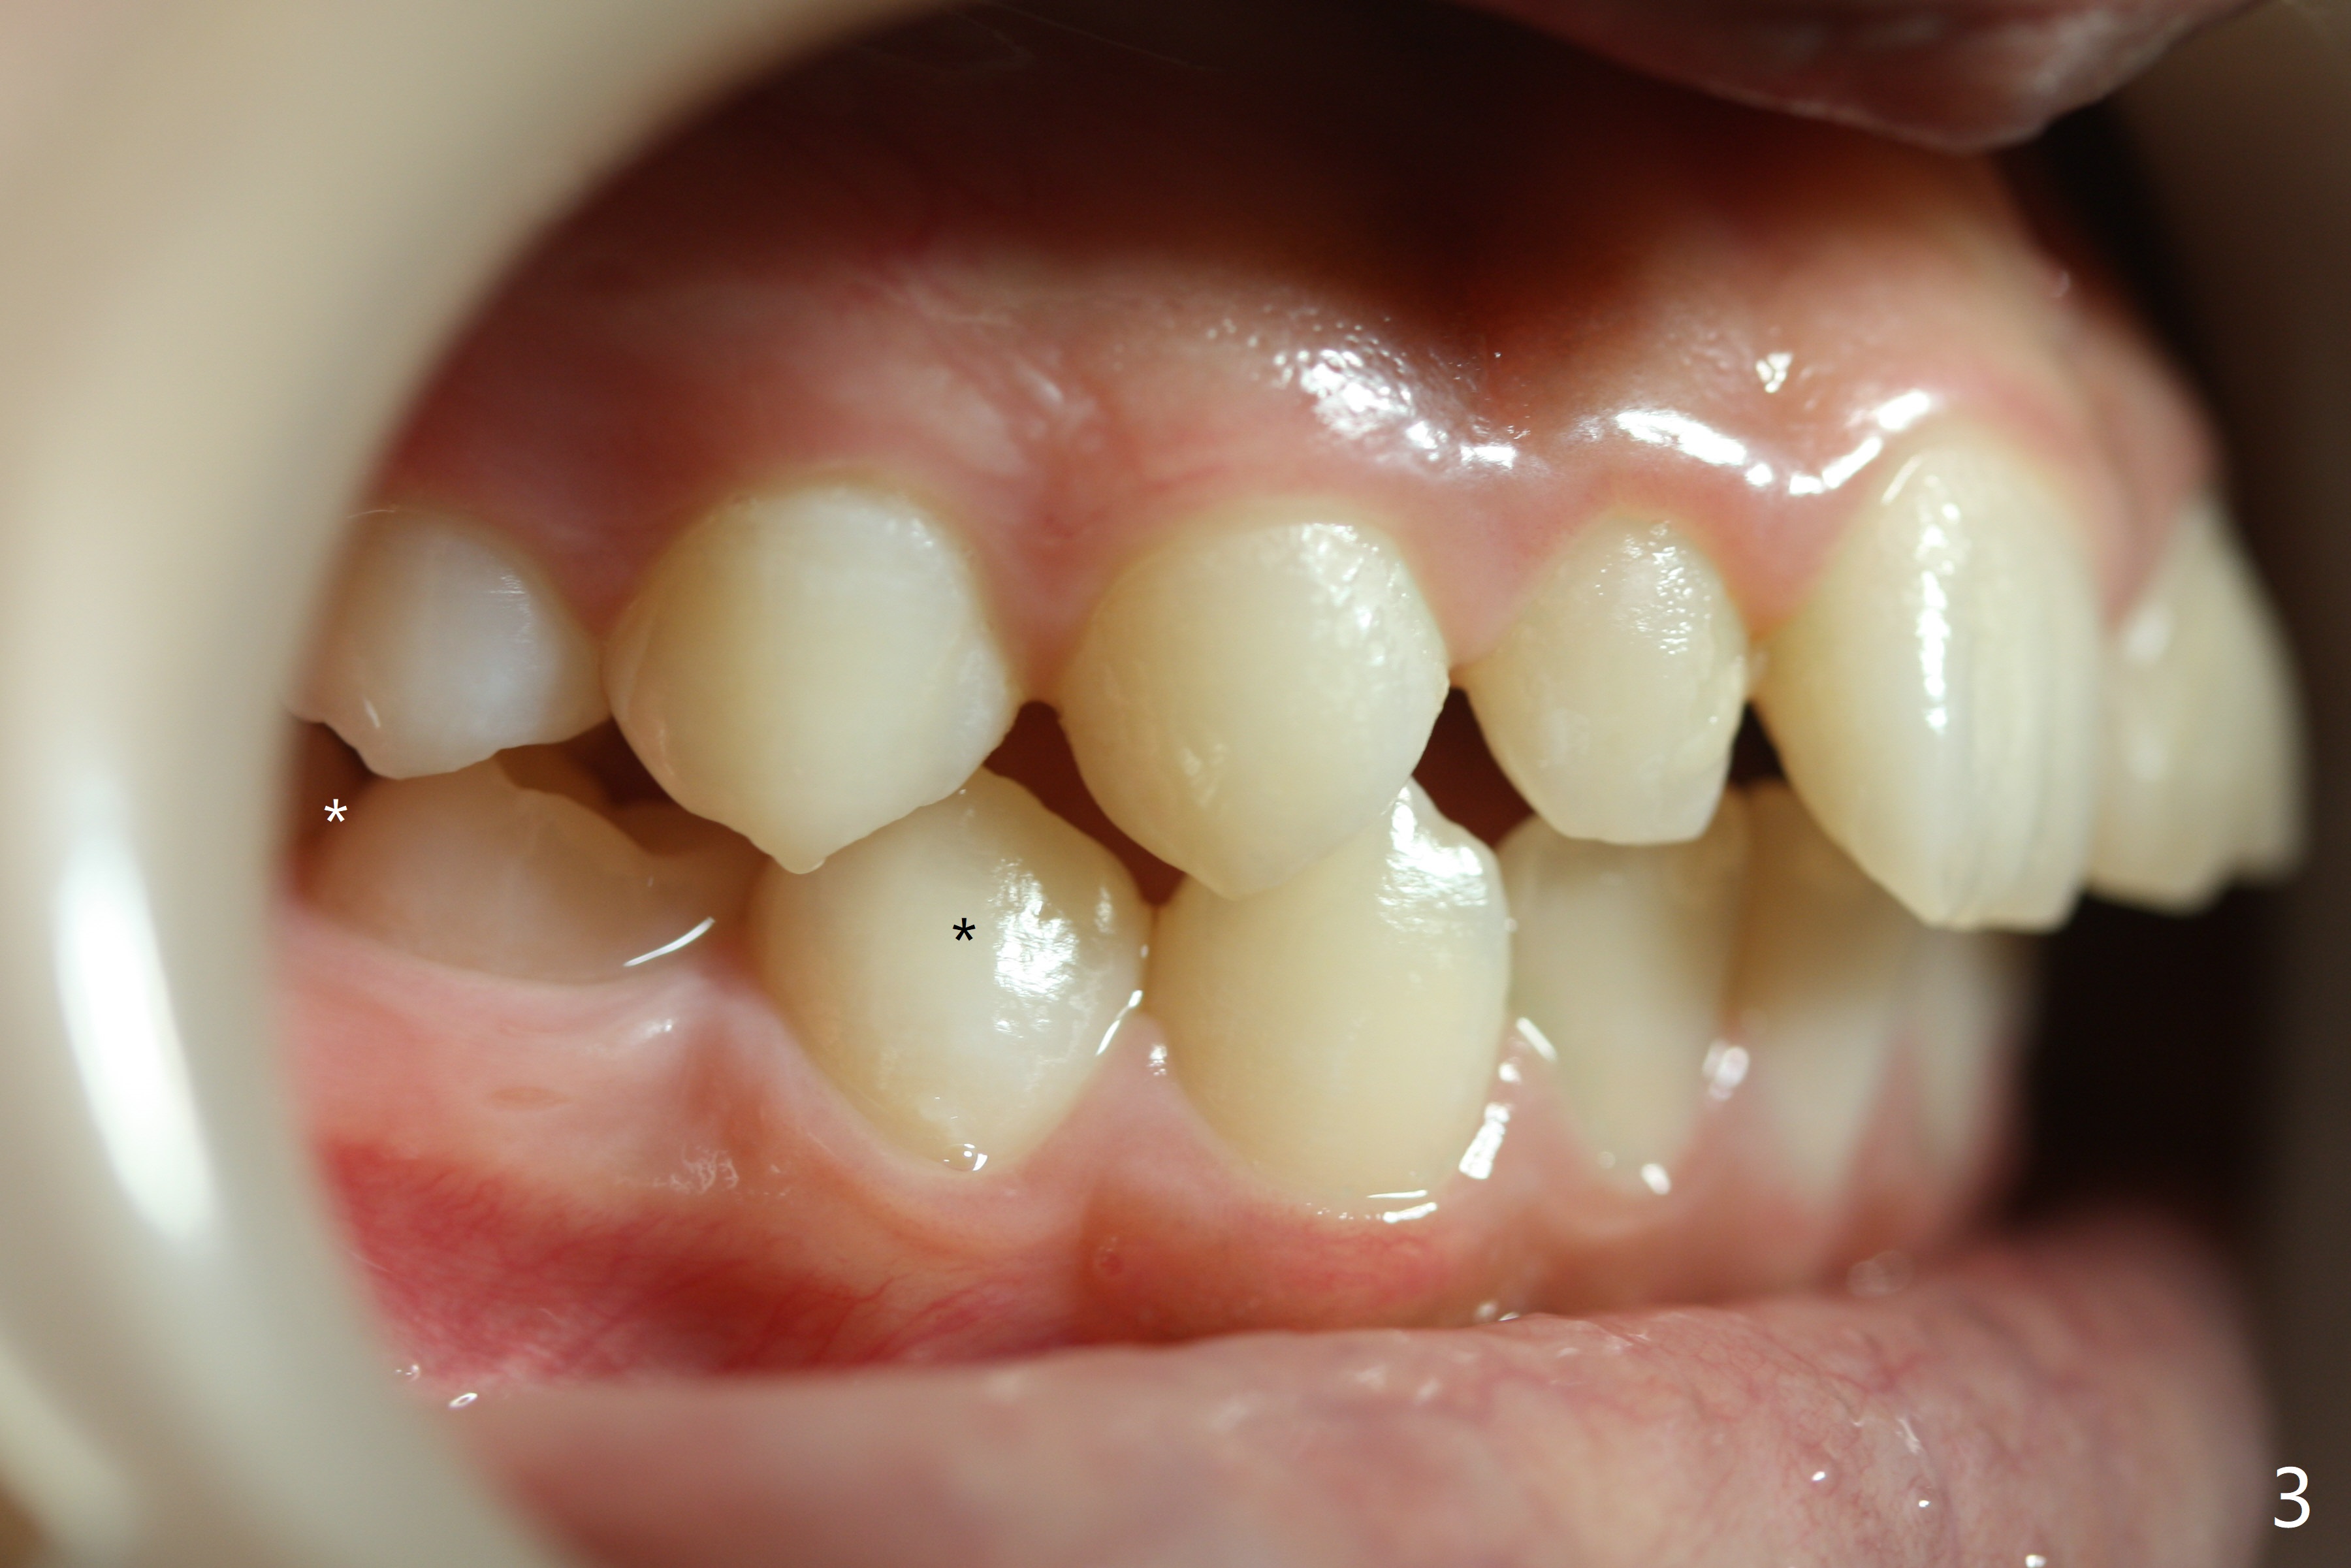

The lower right 2nd bicuspid of a 10-year-old woman seems to rotate before eruption (Fig.1: 5) and remains so when it erupts (Fig.2, at the age of 12).

LR5 rotation appears to be associated with poor interdigitation on the right side (Fig.3), as compared to the left (Fig.4). * in Fig.3-6 indicates height of contour of a lower bicuspid, where a bracket should be placed.